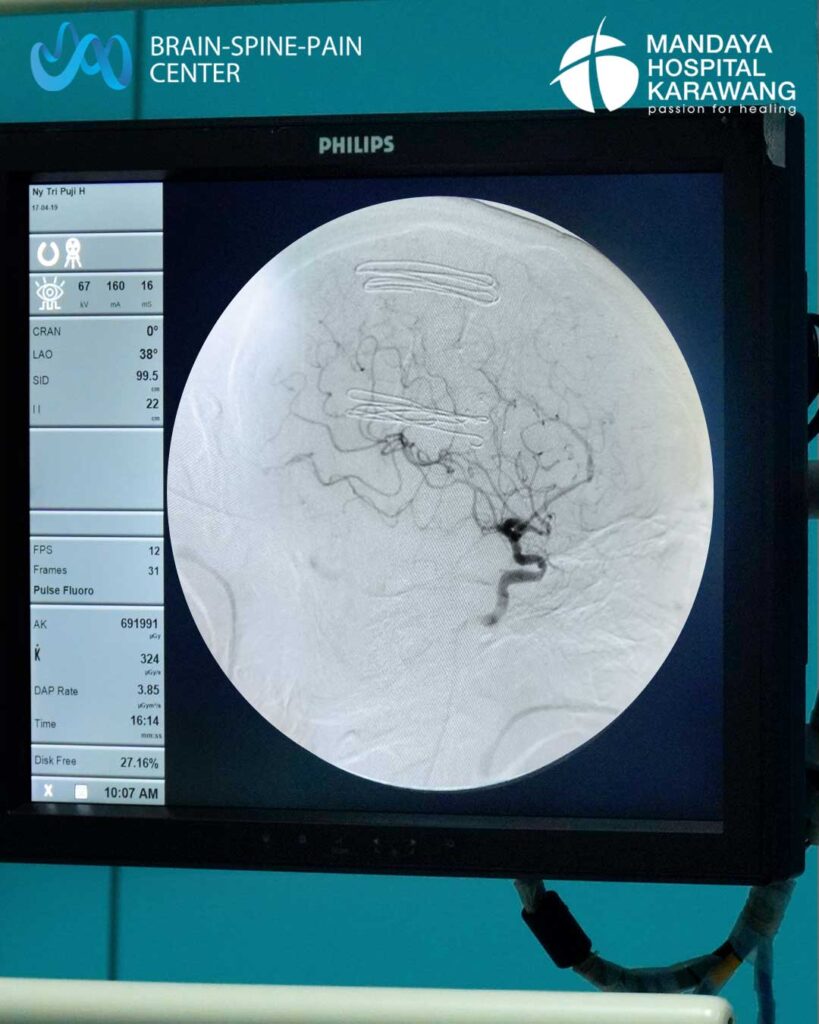

Digital Subtraction Angiography (DSA) otak adalah pemeriksaan radiologi canggih yang digunakan untuk melihat secara detail kondisi pembuluh darah otak. Pemeriksaan ini membantu dokter mendeteksi adanya penyempitan, sumbatan, atau kelainan pembuluh darah seperti aneurisma dan malformasi arteri-vena (AVM).

Melalui teknologi angiografi digital, DSA menampilkan gambaran pembuluh darah dengan sangat jelas, bahkan yang tidak dapat dilihat dengan CT Scan atau MRI biasa.

Dokter biasanya merekomendasikan DSA otak jika pasien mengalami gejala stroke iskemik atau perdarahan otak yang memerlukan penilaian lebih lanjut. Dugaan aneurisma otak (pelebaran dinding pembuluh darah), adanya kelainan sambungan pembuluh darah otak atau AVM (Arteriovenous Malformation), penyempitan pembuluh darah otak yang bisa menyebabkan stroke berulang, serta dari hasil CT/MRI yang menunjukkan kelainan pembuluh darah namun belum jelas penyebabnya.